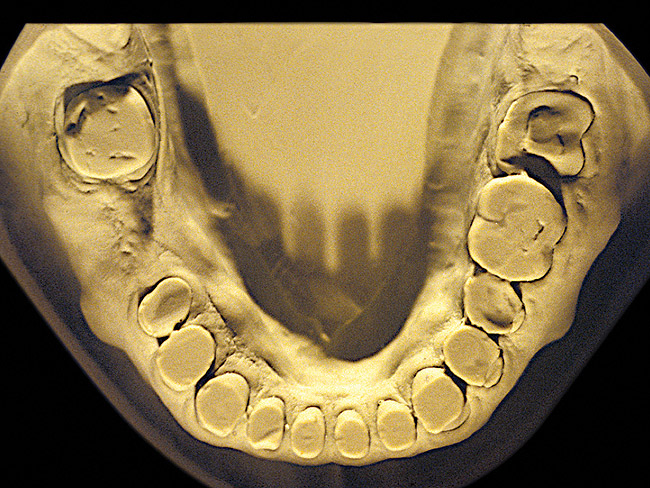

Figure 2  Advanced NCLTS from bruxism, mandibular arch.

Figure 2

The patient shown in Figure 3 and Figure 4 exhibited severe NCLTS from bruxism. Examination of the casts indicated that the NCLTS was progressively greater toward the anterior teeth. Cupping and cratering was not present because there was no secondary cause. Figure 5 and Figure 6 detail another bruxism patient, but to a lesser degree and one with cupping/cratering caused by toothpaste. The cups or craters were not caused from bruxism because the teeth could not touch the bottom of the invaginations. In both featured patients, upon hand-articulating the casts, the NCLTS facets matched up and the diagnosis of bruxism was confirmed.